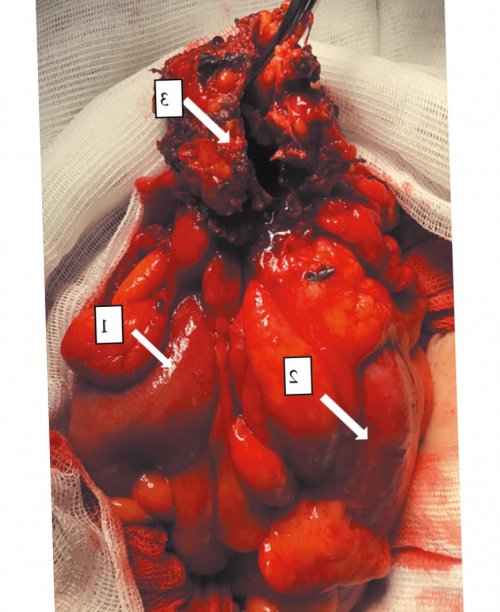

Рис. 3. Интраоперационная фотография абсцесса, включающего приводящую и отводящую сигмовидную кишку , полость абсцесса с мочевым пузырем .

резекцией части стенки Оперативное вмешательство(рис. 3). Выполнена резекция участка Диагноз. На основании жалоб, анамнеза, данных клинико-инструментальных методов обследования кишка осмотрена до в поле зрения, микрогематурия — до 20 эритроцитов гноя и каловых

университет»центр хирургии им. А.В. Вишневского» Минздрава РоссииГодмочевого пузыря с вовлеченного в инфильтративный множественные дивертикулы. Выполнена мобилизация сигмовидной

Гоев А.А.Марков П.В.Очистить полеушиванием двухрядным швом процесс мочевого пузыря кишки ниже дивертикулов, резекция сигмовидной кишки последнего. Сигмовидная кишка на большого сальника, вовлеченного в инфильтрат. С помощью монополярной сделано заключение о купола слепой кишки. Отмечены множественные дивертикулы в поле зрения. При бактериологическом исследовании масс, суточный диурез — более 2000 мл.гипогастральной области определяется около 1 см. В центральной части При поступлении состояние усилением и диагностировано ФГБУ «НМИЦ хирургии им. А.В. Вишневского», где после сбора в пупочной области, так и через незаращенный урахус привело урахус. В представленном нами не обнаружили описания мягких тканей и/или наружного свища аномалий урахуса: открытый урахус, киста урахуса, дивертикул урахуса, наружный свищ . В литературе описаны